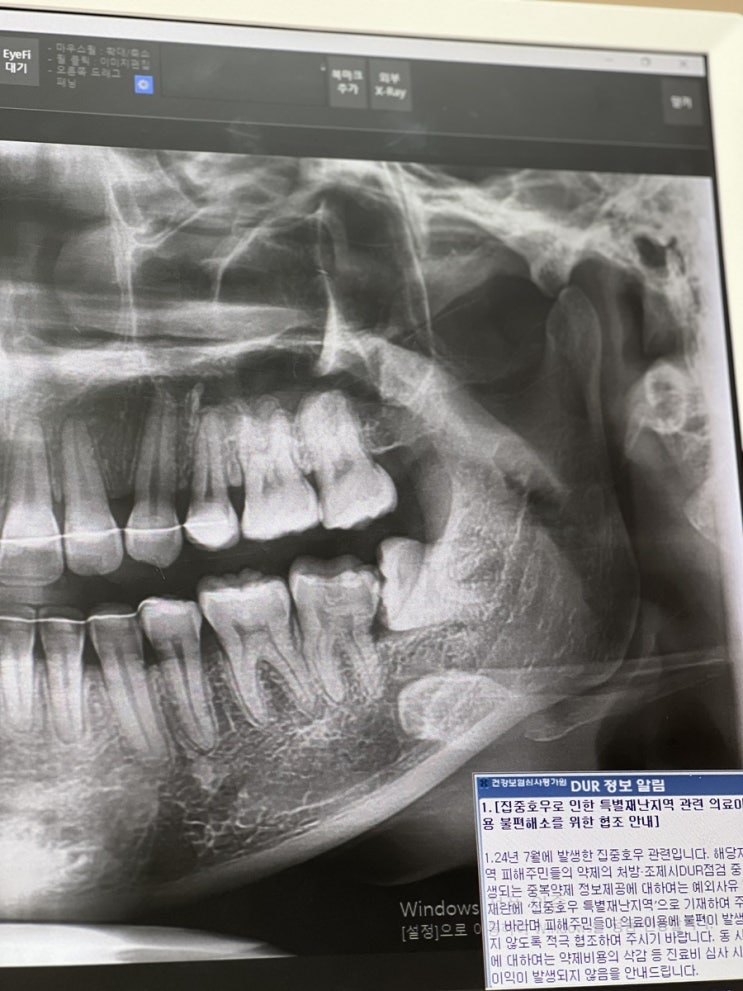

강남역치과 매복사랑니 발치 후기?

안녕하세요 여러분-! 사랑니 발치 해야지~~해야지~~ 하다가 어느새 13년이 흘러버렸습니다..? 사실은 고등...